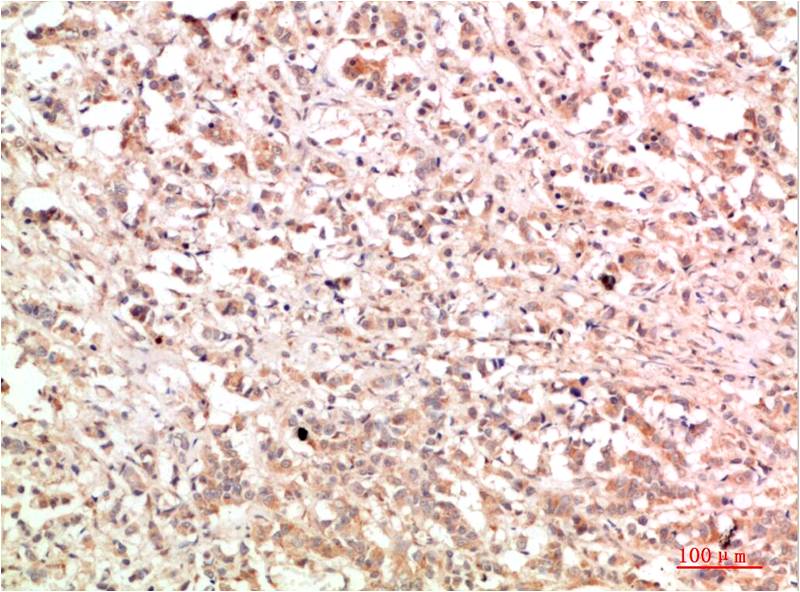

STAT1 Rabbit Polyclonal Antibody

Applications :WB, IHC

| Recommended dilutions: | WB:1:1,000-2,000 IHC:1:200-500 |

| Specificity: | Antibody can detects endogenous STAT1 protein. |